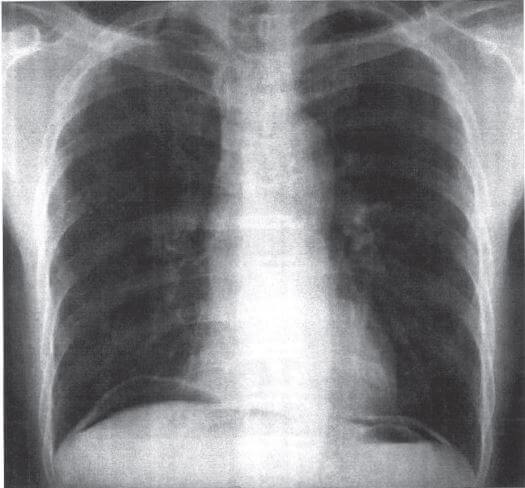

問題54.25歳の男性。バイク運転中に転倒し救急外来に搬入された。来院時上腹部痛を訴えた。施行した立位胸部エックス線写真を下に示す。

所見として正しいのはどれか。

4.腹腔内遊離ガス

解答4

1.× 心拡大(心胸比50%以上)の場合、心陰影が胸郭幅の半分以上を占めるように見られる。

2.× 胸水貯留は、①CPangle(肋骨横隔膜角)が、90°よりも大きい(鈍い)場合や消失していたりする所見で疑われる。ちなみに、胸水貯留は心不全などで生じる。

3.× 横隔膜ヘルニアの場合、胃泡や腸管ガス像が胸腔内に連続して見える

横隔膜ヘルニアとは、生まれつき横隔膜に欠損孔があって、本来お腹の中にあるべき腹部臓器の一部が胸の中に脱出してしまう病気である。多くの場合、横隔膜の後外側を中心に生じるボホダレク孔が欠損孔であるため、別名ボホダレク孔ヘルニアとも呼ばれる。

4.〇 正しい。腹腔内遊離ガスの所見が認められる。

・腹腔内遊離ガス像とは、腹腔内フリーエアーともいい、腹腔内に空気がたまることである。本来、腹腔内の空間には空気がない。しかし、消化管(胃や大腸など)に穴が開くと中の空気が腹腔内に漏れ出す。この時、胸部レントゲンを立位で撮影すると、腹腔内にある空気が上に集まり、横隔膜の下(腹腔内)に空気がたまる。